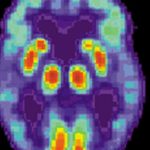

Un team internazionale di ematologi, tra cui Guy Young del Children’s Hospital Los Angeles, ha scoperto che nei pazienti con emofilia A, una nuova terapia chiamata Emicizumab, riduce l’incidenza di episodi di emorragia dell’87%.

Emicizumab è un nuovo anticorpo monoclonale che viene somministrato per via sottocutanea una volta alla settimana. Secondo Alan S. Wayne MD, Direttore del Centro per il cancro e le malattie del sangue, “Questa ricerca rappresenta un importante passo avanti per gli individui con emofilia A che non rispondono più alle terapie convenzionali di coagulazione. Questa nuova terapia è notevolmente più efficace del trattamento standard per prevenire il sanguinamento, è più facile da somministrare, richiede una dose minore ed ha un buon  profilo di sicurezza”.

Lo studio ha arruolato per la sperimentazione, 109 ragazzi dell’età di 12 anni con l’emofilia A ed ha dimostrato che i pazienti trattati con emicizumab hanno sperimentato l’ 87% di riduzione degli eventi di emorragia rispetto ai pazienti non trattati che hanno avuto una riduzione del 79%. Non sono stati rilevati anticorpi anti-farmaco.

“Questo è il risultato più significativo che ho visto durante i miei 20 anni di lavoro nel campo dell’emofilia”, ha detto Young, che è anche Professore di pediatria presso la Keck School of Medicine della USC e tratta i pazienti pediatrici con emofilia in California.